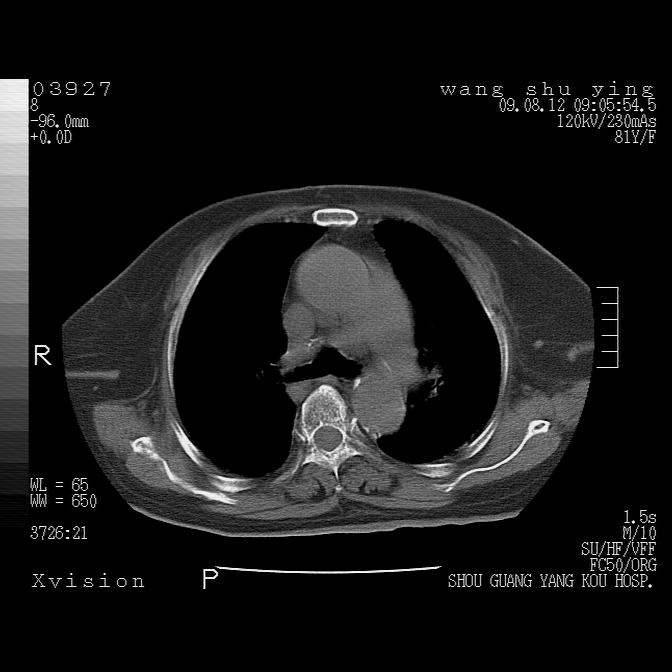

以下是引用帅河马在2009-8-12 12:59:00的发言:[br]两肺感染性病变伴双侧胸膜肥厚。[br]左侧甲状腺腺瘤不除外。[br]腹水+心包积液。[br][br][本贴已被 帅河马 于 2009-8-12 13:14:32 修改过]

以下是引用sdzyy在2009-8-12 18:17:00的发言:[br]两肺感染性病变伴双侧胸膜肥厚。[br]左侧甲状腺腺瘤不除外。[br]腹水+心包积液。[br]支持

以下是引用随光逐影在2009-8-12 19:42:00的发言:[br]1)两肺感染性病变伴双侧胸膜肥厚。2)不排除左侧甲状腺腺瘤。3)肝脏占位性病变;建议行进一步检查。